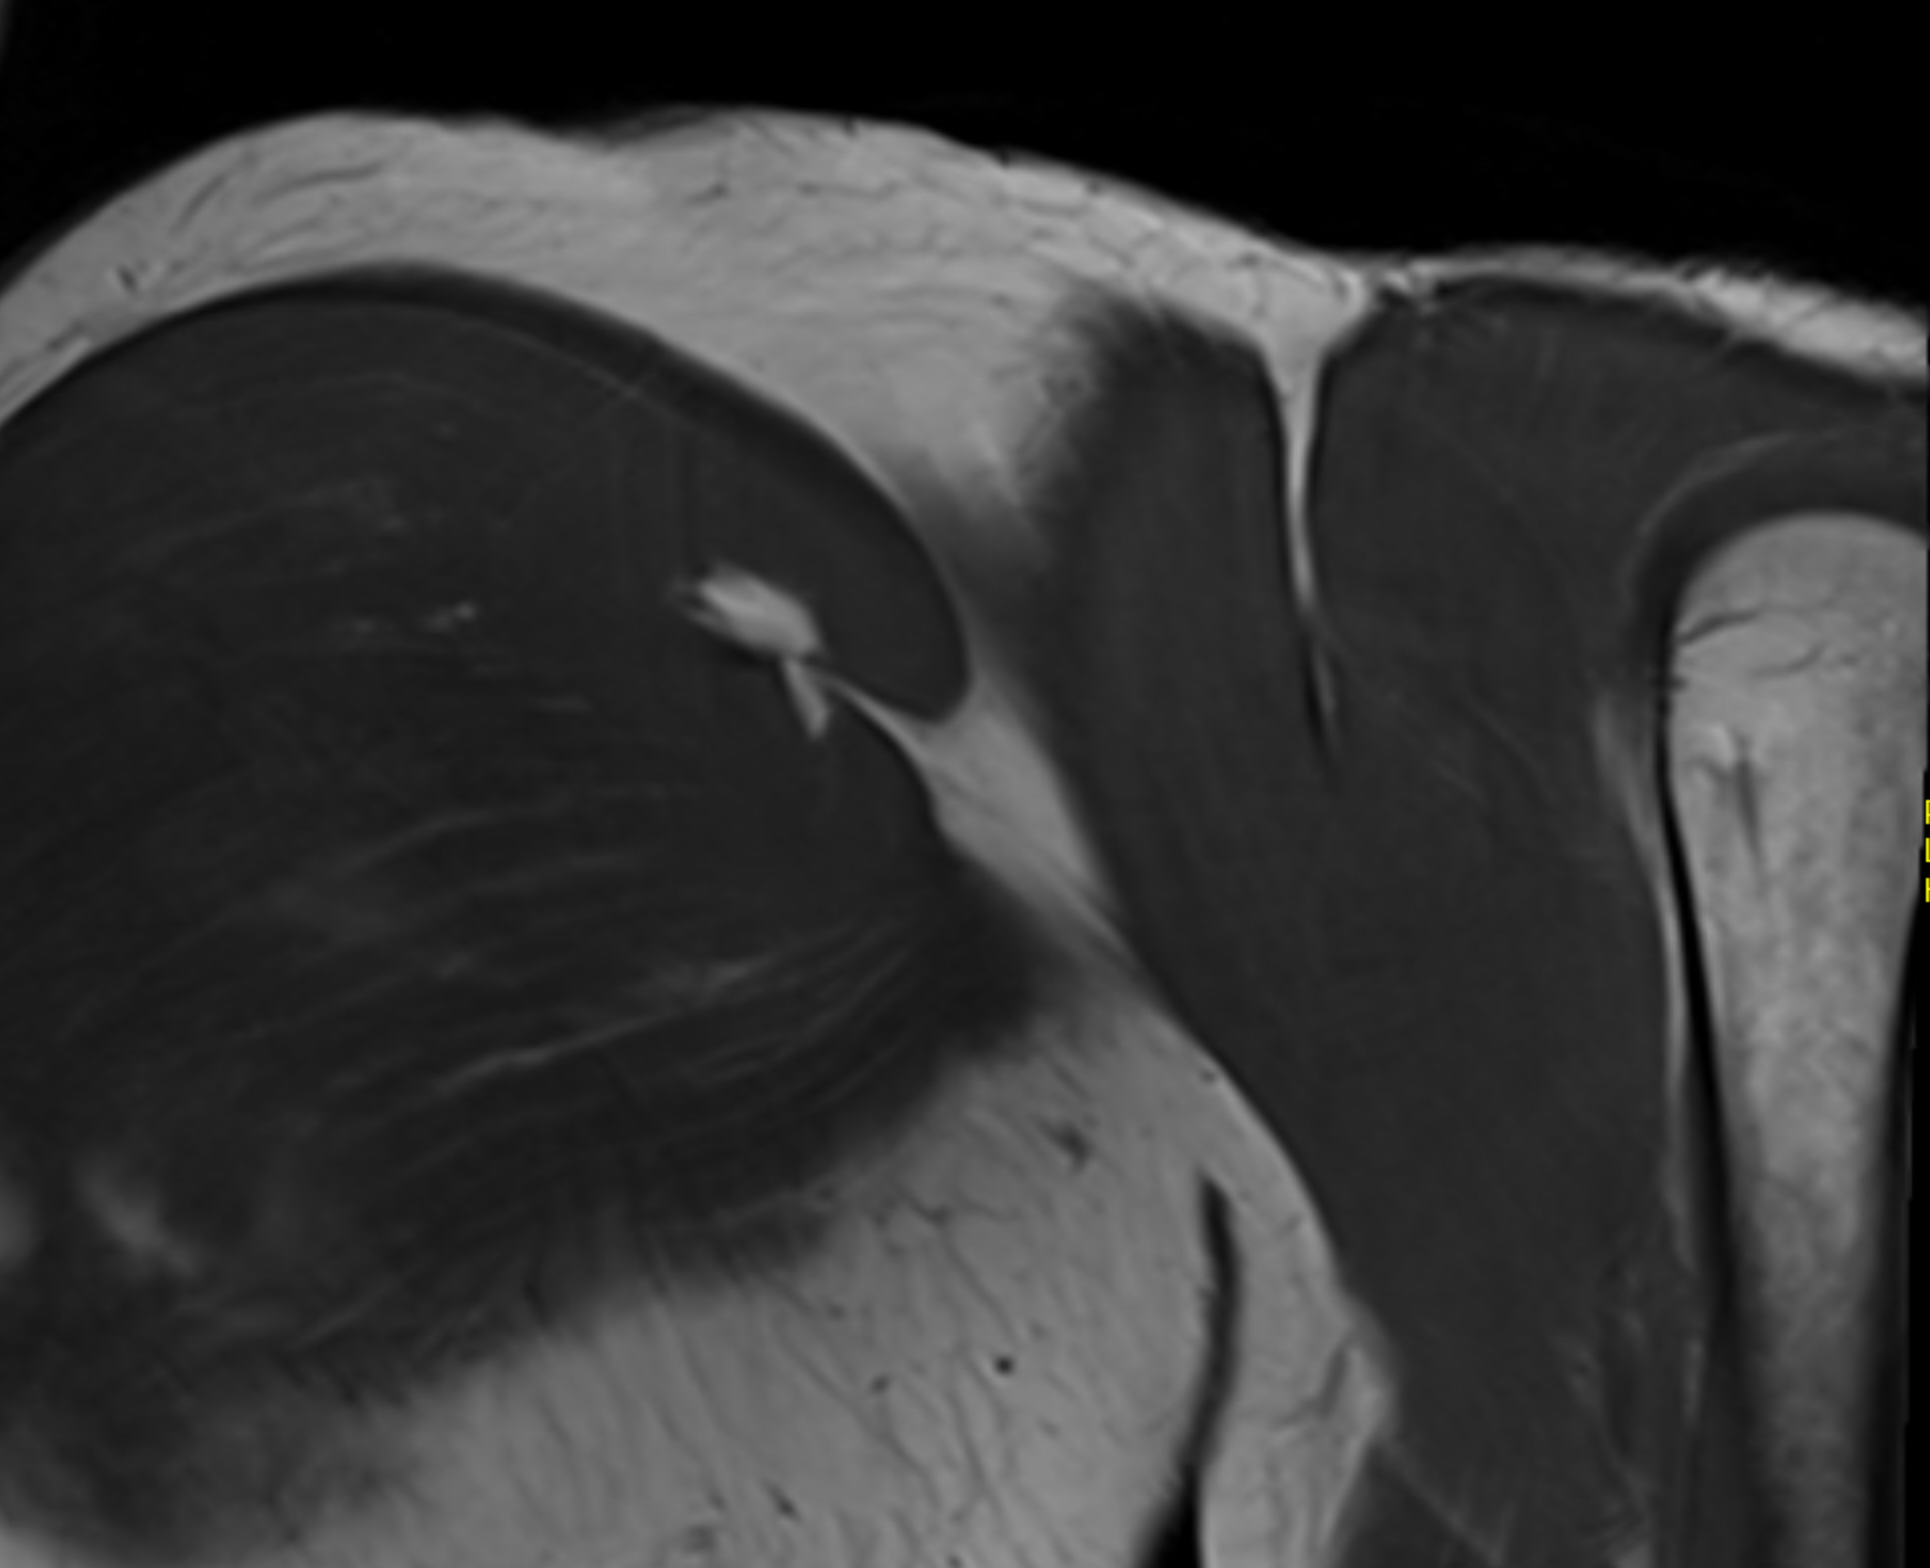

MRI P Major tear 1MRI Pec major tear 2

Coronal T2 MRI Right shoulder demonstrating musculotendinous avulsion